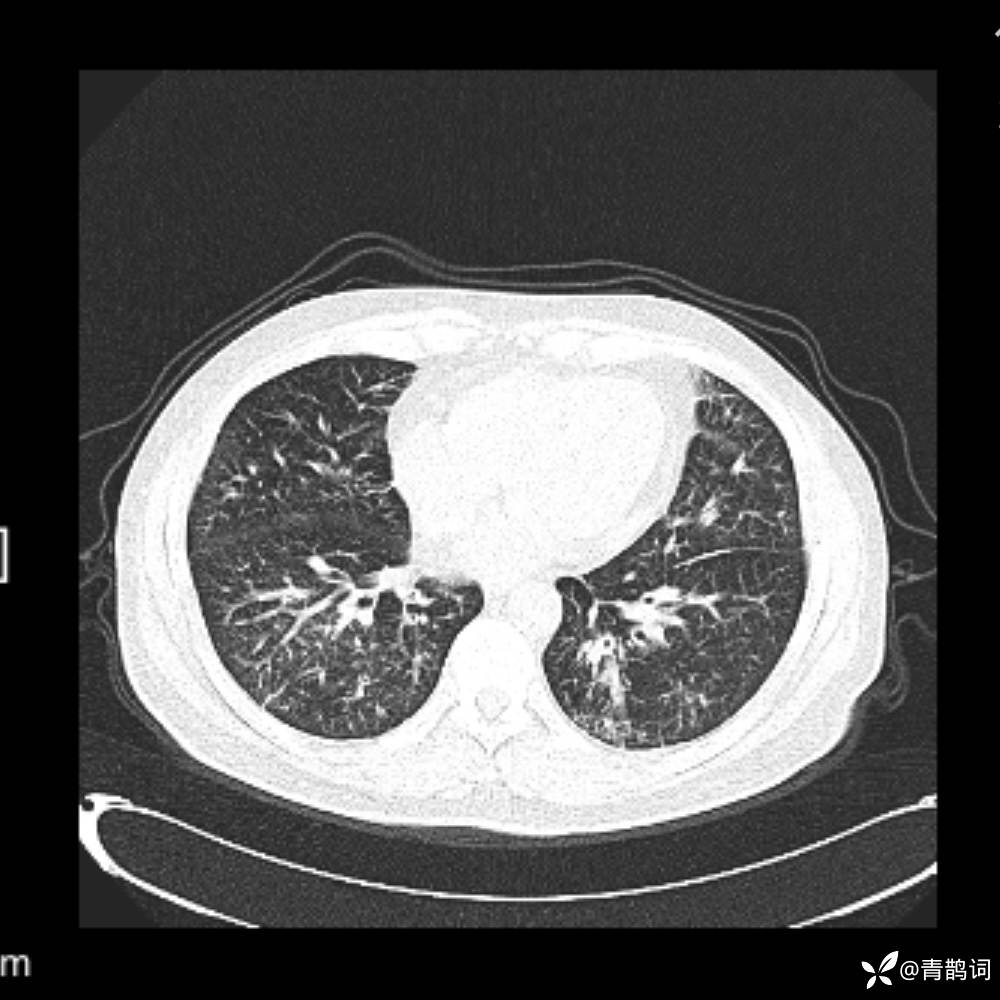

患者年龄:30岁。

患者性别:男。

简要病史:左颜面部肿胀2年,反复咳嗽咳痰,逐渐加重。

辅助检查

结合病史及影像学表现,期待评论区各位老师各抒己见~